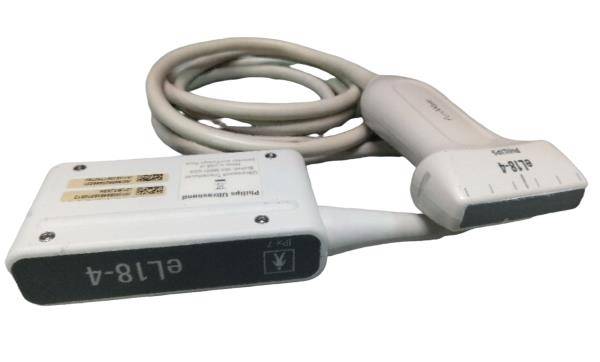

Description

Condition: Used: An item that has been used previously. The item may have some signs of cosmetic wear, but is fully operational and functions as intended. This item may be a floor model or store return that has been used. See the sellerâs listing for full details and description of any imperfections. See all condition definitions- opens in a new window or tab ... Read moreabout the condition

Brand: GE

Model: 4C-RS